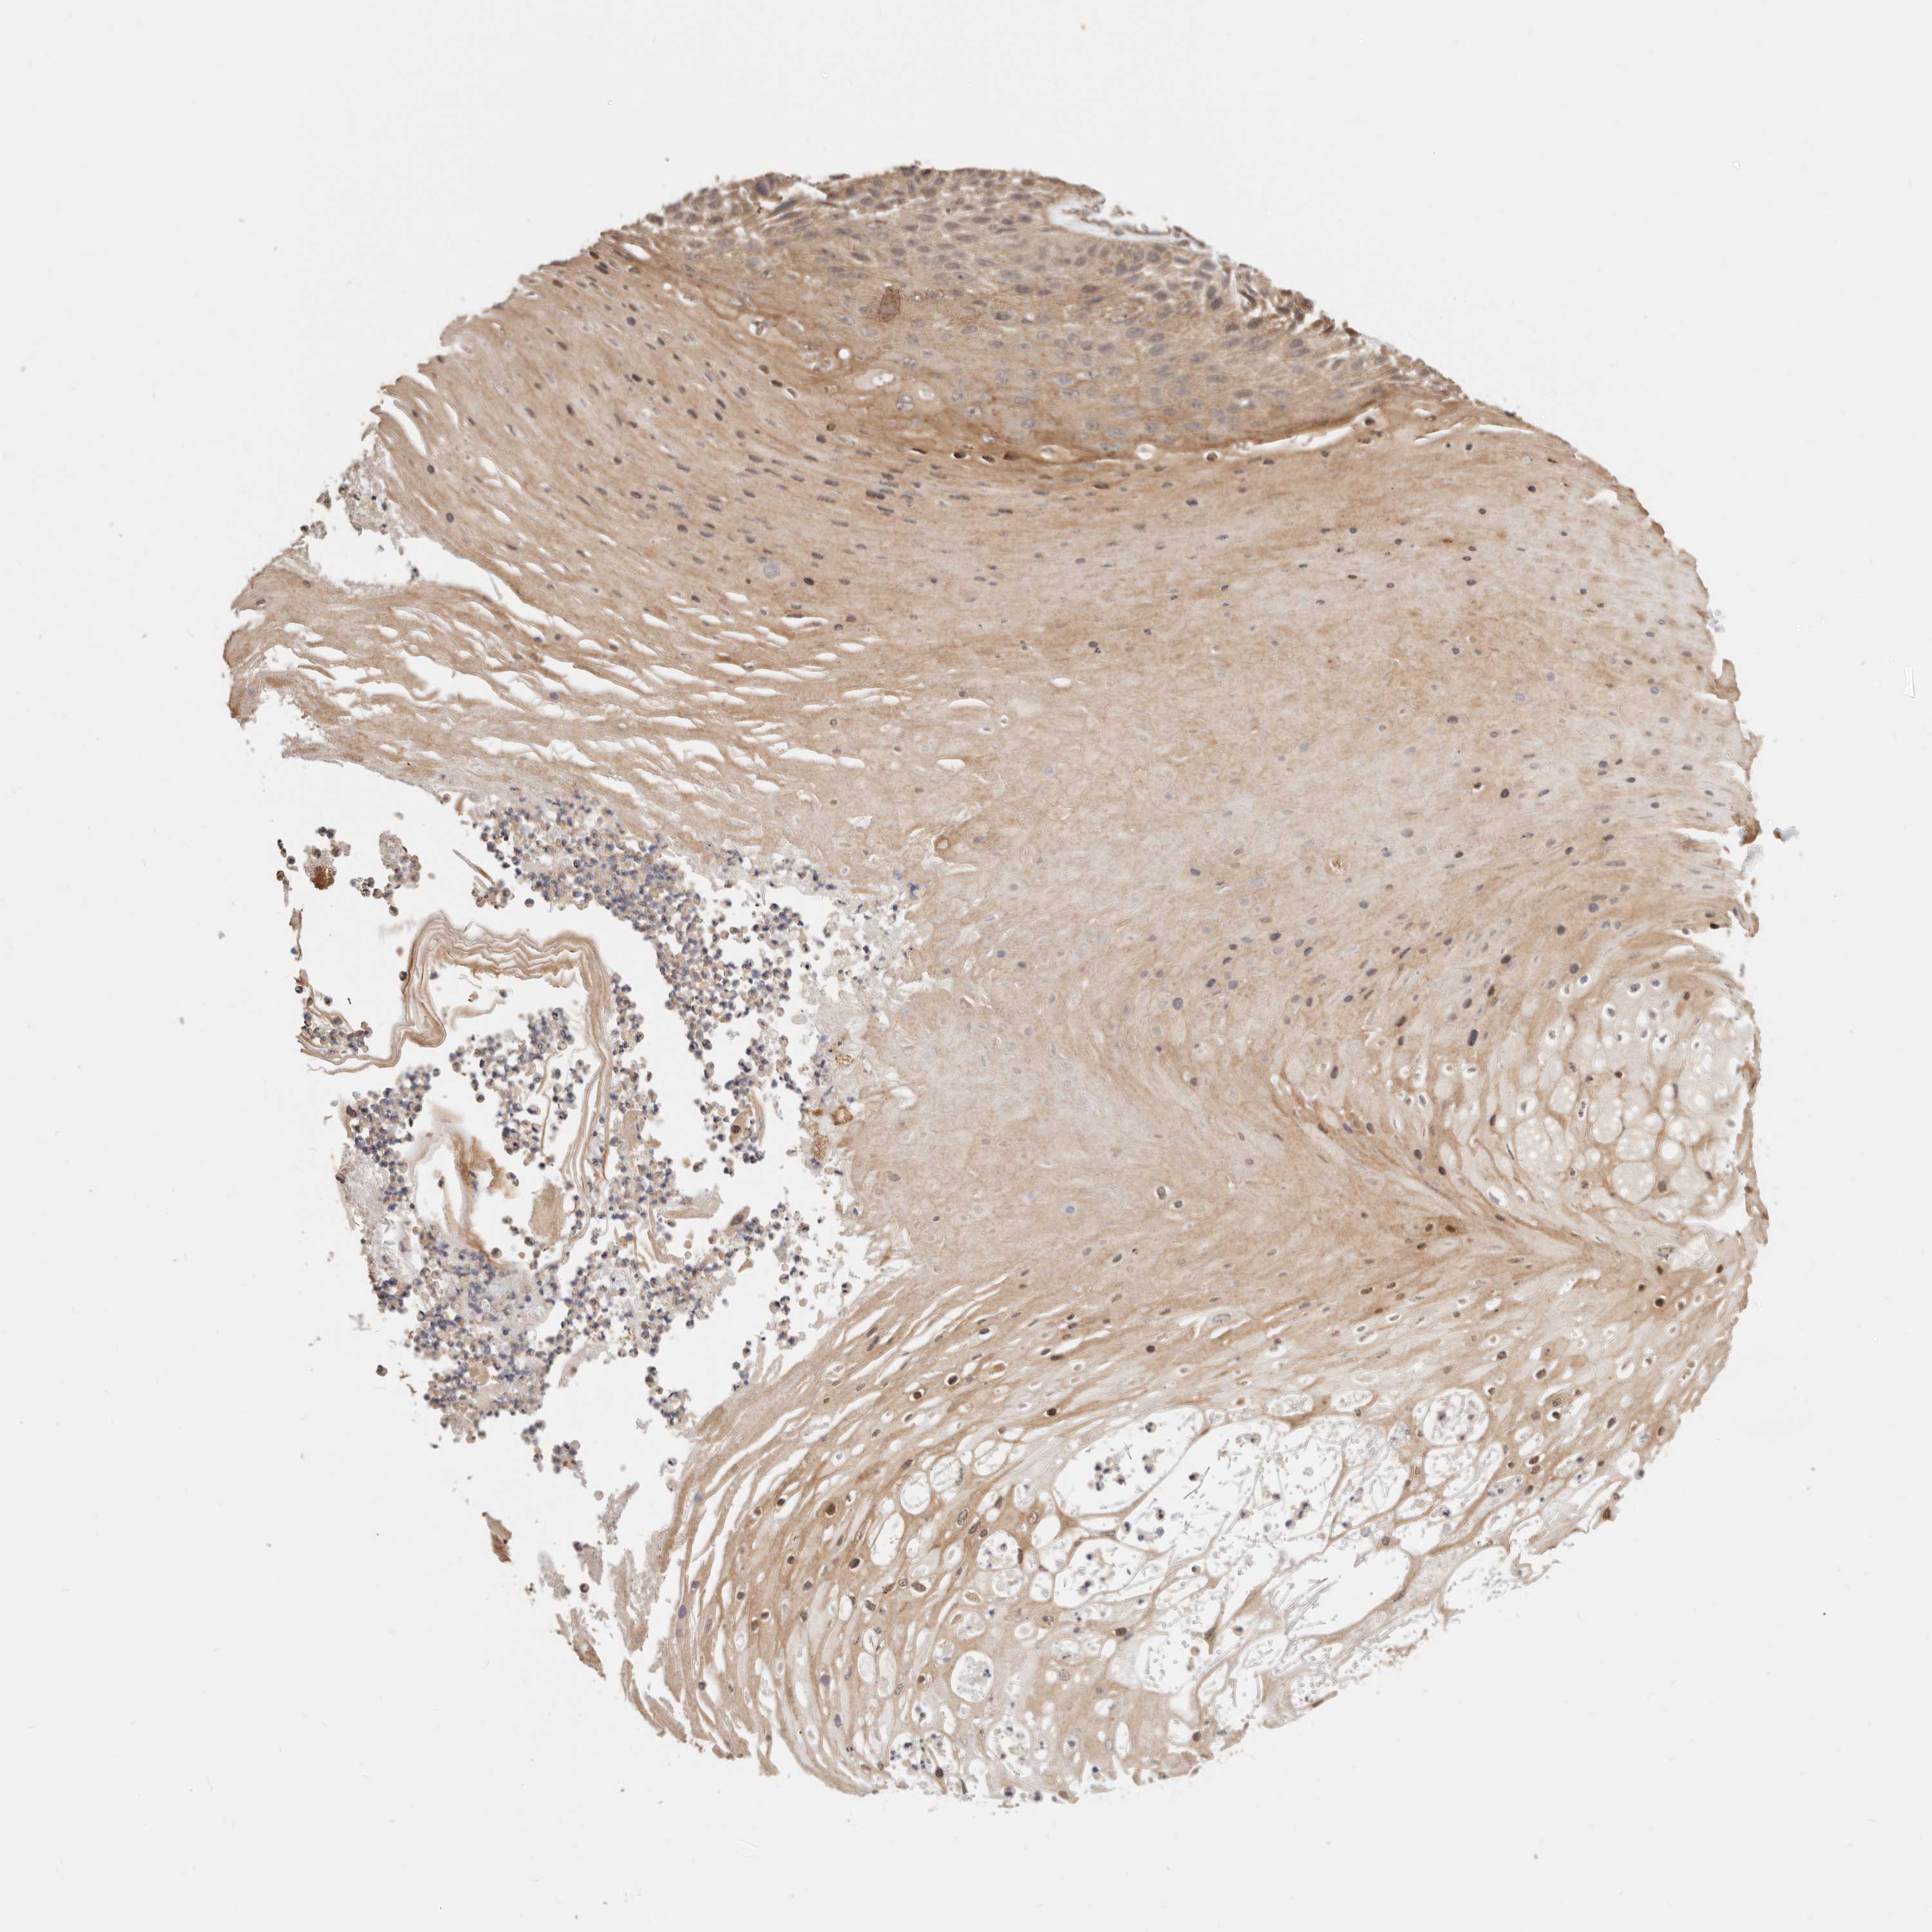

SKIN CANCER - Protein expressioni

A mouse-over function shows sample information and annotation data. Click on an image to view it in a full screen mode. Samples can be filtered based on level of antibody staining by selecting one or several of the following categories: high, medium, low and not detected. The assay and annotation is described here.

Antibody stainingi

Antibody staining in the annotated cell types in the current human tissue is reported as not detected, low, medium, or high, based on conventional immunohistochemistry profiling in selected tissues. This score is based on the combination of the staining intensity and fraction of stained cells.

Each image is clickable and will lead to virtual microscopy that enables deeper exploration of all samples and also displays staining intensity scores, fraction scores and subcellular localization as well as patient and tissue information for each sample.

HPA030212

HPA030213

HPA030214

HPA030215

CAB013496

Basal cell carcinoma

Squamous cell carcinoma, NOS

Squamous cell carcinoma, metastatic, NOS

Adnexal tumor, benign